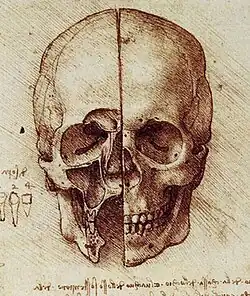

Anatomie

Erste moderne anatomische Zeichnungen von Kiefer, Zähnen und Kaumuskulatur fertigte Leonardo da Vinci (1452–1512) an. Zudem schuf er Skizzen zur Anatomie des Gesichtes und der Kieferhöhle.[112] Einer der Begründer der Anatomie war Andreas Vesalius, der mit seinem Anatomiewerk De humani corporis fabrica libri septem von 1543 die Ansichten der antiken Autorität Galen von Pergamon in Frage stellte. Vesal stützte sich bei seinen anatomischen Erkenntnissen, die die neuzeitliche Anatomie begründeten, auf die Sektion von menschlichen Leichen, während Galen seine (fehlerhaften) Erkenntnisse noch durch das Sezieren von Tieren gewann. Durch ihn erfolgte die Erstbeschreibung der Gelenkbänder und Zwischengelenkknorpel des Kiefergelenks. Ferner erörterte er sehr genau die Funktion der Muskeln von Gesicht und Wange, gab eine exakte Anatomie der Zahnwurzeln und erkannte als erster die Pulpahöhle, jedoch nicht ihre Funktion.[113] Bartolomeo Eustachi (1500/1513–1574), war der erste, der die erste und zweite Dentition genauer untersucht hat und 1550[114] auch die Funktion der Pulpahöhle beschrieb.[115][116]

Leonardo da Vinci Schädelskizze

Leonardo da Vinci Schädelskizze -